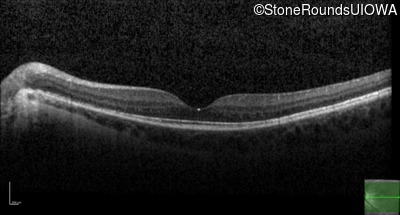

Optical Coherence Tomography - Left - 20/50

Exemplar / OCT Stack